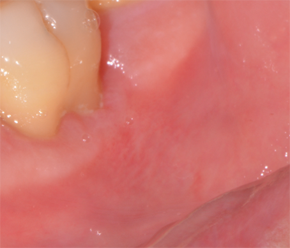

세 번째로는 자극으로 인해 일어나는 구내염입니다. 그 원인들에는 뺨, 혀, 입술을 깨물었거나 교정기 또는 구강 내에 기구를 착용, 날카로운 치아, 뜨거운 음료나 음식, 잇몸 질환, 구강 감염, 씹는담배, 음식이나 의약품 과민증, 자가 면역 질환(루푸스, 크론병, 베체트병 등), 특정 약물 복용(항생제, 루마티스 관절염 약, 간질 약 등), 방사선 치료 등이 있습니다.